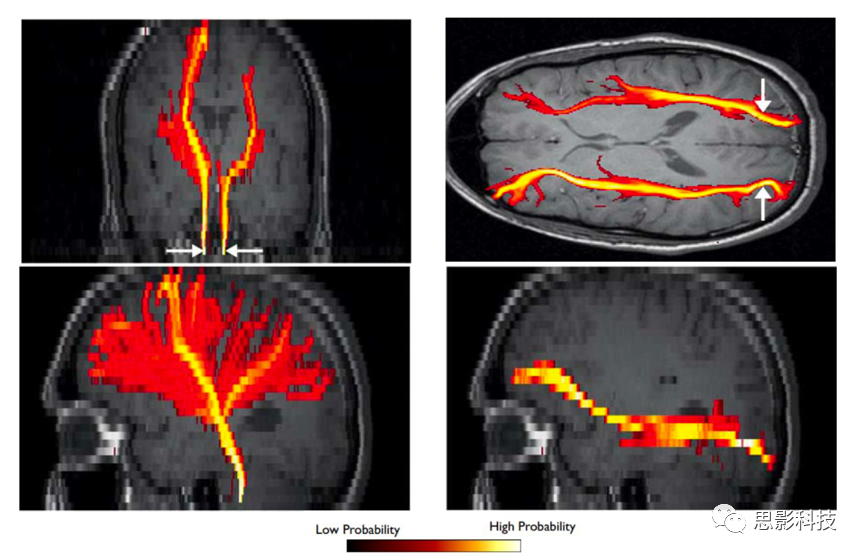

圖例:概率性纖維追蹤

7、概率性纖維自動(dòng)提取方法(AutoPtx

通過(guò)預(yù)先設(shè)定好纖維束的種子點(diǎn)、排除腦區(qū)、終止腦區(qū)等條件,可對(duì)概率性纖維束進(jìn)行自動(dòng)分段提取并進(jìn)一步計(jì)算對(duì)應(yīng)的平均標(biāo)量指標(biāo)(FA、MD等)。

圖例:概率性纖維自動(dòng)提取技術(shù)在老化研究中的應(yīng)用